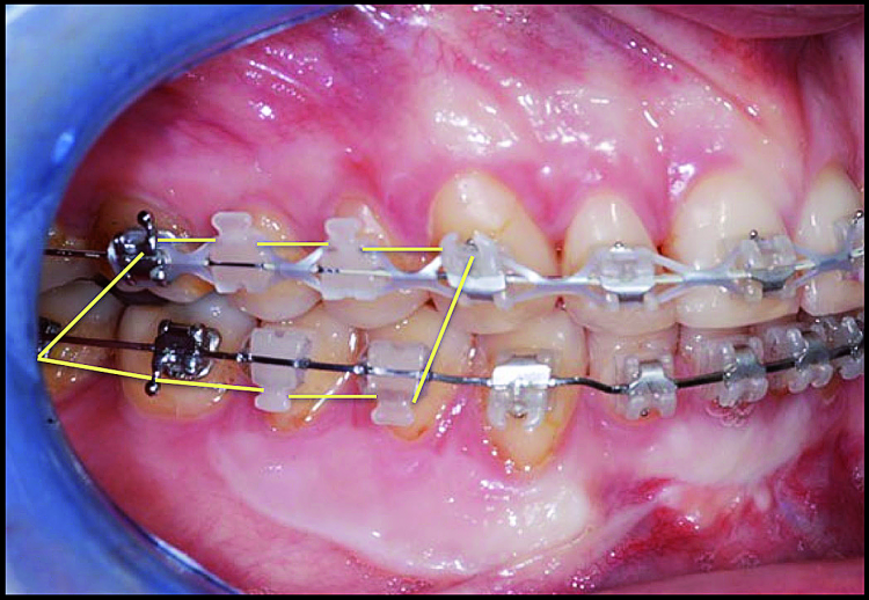

BiTurbo2 system for rapid deep overbite correction